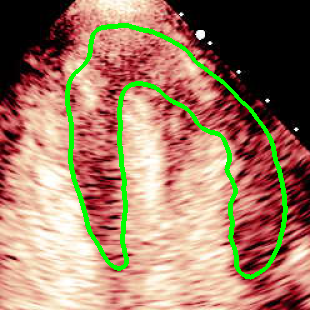

For variations caused by low quality images such as those of low resolution or significant artifacts, however, the unique ground truth may not be available. Take the myocardial segmentation task of Myocardial Contrast Echocardiography (MCE) as an example. An inter-observer experiment was conducted among five experienced cardiologists, and Fig. 1(a)(b) visualize the annotations of two images from three of these cardiologists. It can be seen that the labels by different cardiologists vary significantly, especially in locations where the intensity information of myocardium is very similar to the background. Table 1 shows the average Dice of the annotation of each cardiologist, using one of the others’ as the ground truth, over 180 images. We can observe that none of the Dice is above 0.9, some even under 0.8, confirming significant variations among the annotations. In this case, as the variations are caused by the image quality, even these cardiologists cannot tell which annotation is better than others, and a majority vote for ground truth would not make sense sometimes as can be seen in Fig. 1(c)(d). For this reason, we cannot obtain a unique ground truth in the evaluation process and the traditional metrics such as Dice and IoU cannot be used.